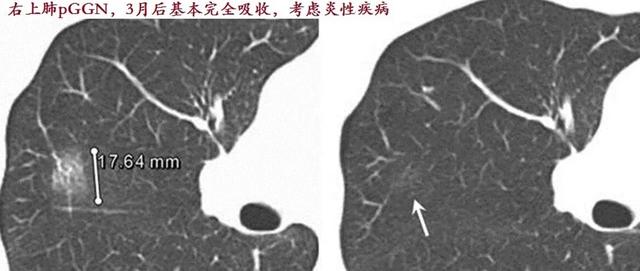

1.一过性磨玻璃结节

一过性磨玻璃结节就是指一开始肺部ct发现有磨玻璃结节,但是经过消炎吃药之后,磨玻璃结节消失了。相信很多朋友都有这种经历。这种磨玻璃结节,称之为一过性磨玻璃结节,都是细菌感染引起的。通过治疗之后都是可以完全治愈的。

2.持续性良性磨玻璃结节

持续存在的良性磨玻璃的结节。基本都是局部肺组织纤维化,他形成的原因还是与急性的炎症期没有正规的消炎导致进入到慢性期形成纤维化,从而不能够完全吸收。占持续存在的磨玻璃结节百分之30~40。